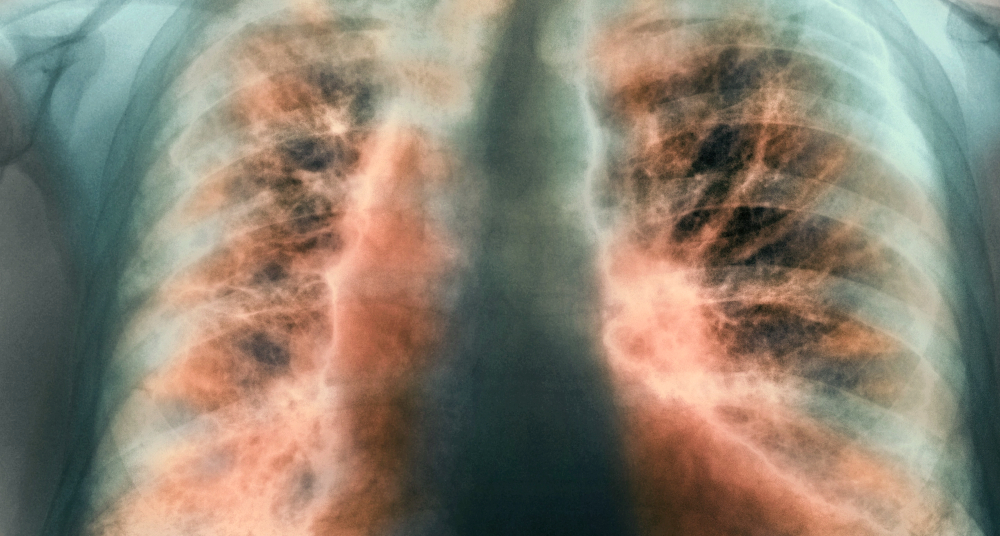

Vročina se lahko ponavlja ves čas bolezni. Sarkoidoza najbolj prizadene pljuča. Na rentgenogramu utegnejo biti vidne povečane bezgavke na mestu, kjer se pljuča stikajo s srcem, ali na desni strani sapnika. Sarkoidoza v pljučih izzove vnetje, ki lahko končno privede do brazgotinjenja in nastanka cist ter povzroča kašelj in težko dihanje. Huda prizadetost pljuč lahko sčasoma oslabi srce.

Slika: Sarkoidozo pogosto odkrijejo na rentgenogramu prsnih organov.

Zdravniki sarkoidozo najpogosteje prepoznajo po značilnem rentgenskem zasenčenju. Včasih dodatne preiskave niso potrebne. Če so, diagnozo potrdi mikroskopski pregled tkiva, ki pokaže vnetje in granulome.